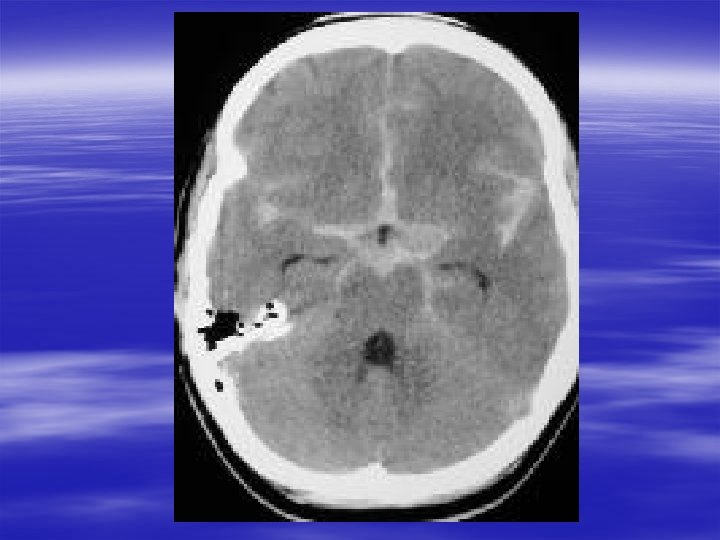

Specific Head Injuries § Penetrating Injury – Gunshot Wounds § Injury due to direct brain injury and cavitary effects § GCS predicts prognosis – GCS >8 and reactive pupils = 25% mortality – GCS <5 = nears 100% mortality – Stab wounds